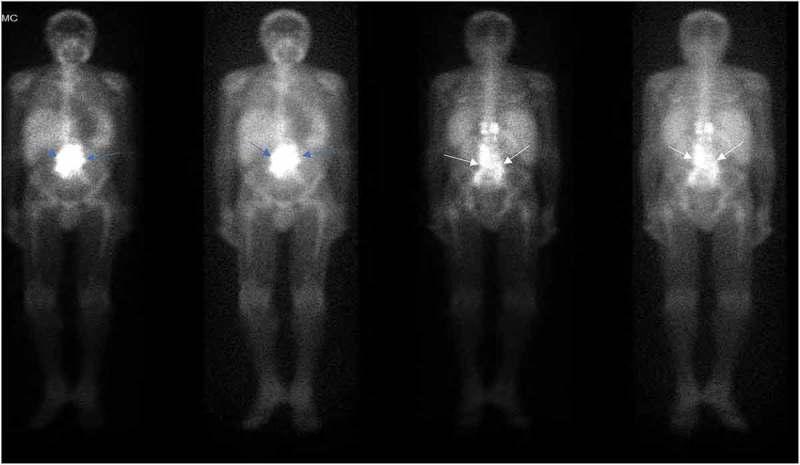

Nontuberculous mycobacterium is a recognized cause of hypercalcemia, particularly in patients with acquired immunodeficiency syndrome (AIDS). Here we describe a case of severe hypercalcemia secondary to () in a patient with AIDS. To the best of our knowledge this is the first case report describing a case of presenting as retroperitoneal lymphadenopathy and severe hypercalcemia. : A 56-year-old man with AIDS presented with altered mental status and somnolence for four days. Laboratory investigations were significant for calcium 16.49 mg/dL (RI 8.9-10.3 mg/dL), 1,25 dihydroxyvitamin D level 44.1 pg/ml (RI 19.9-79.3 pg/ml) and parathyroid hormone (PTH) 4 pg/mL (RI 15-65 pg/mL). CT scan of Abdomen and Pelvis showed hepatosplenomegaly with large retroperitoneal, retrocrural, and mesenteric lymphadenopathy which had an intense focal uptake on Gallium scan. Bone marrow biopsy revealed mild plasmacytosis (5%) with no evidence of myelodysplasia, acute leukemia or lymphoma. A subsequent lymph node biopsy showed fragments of fibrous tissue with lymphohistiocytic infiltrate and many acid-fast bacilli. Pre-antibiotic blood cultures grew which was identified later as at four weeks. : hypercalcemia in HIV-infected patients may suggest malignancy or infectious etiology, among other causes. Clinicians should be aware of the risk of hypercalcemia with nontuberculous mycobacterium (NTM) infection, whether as first manifestation or a late presenter in the disease course after initiating antiretroviral therapy (ART). We suggest careful monitoring of serum calcium level upon diagnosis of NTM infection and after initiation of ART, NTM therapy or vitamin D supplementation.

非结核分枝杆菌是高钙血症的一种公认病因,尤其是在获得性免疫缺陷综合征(AIDS)患者中。在此,我们描述了一例AIDS患者继发于()的严重高钙血症病例。据我们所知,这是首例描述()表现为腹膜后淋巴结病和严重高钙血症的病例报告。病例报告:一名56岁的AIDS男性患者出现精神状态改变和嗜睡4天。实验室检查显示血钙16.49mg/dL(参考区间8.9 - 10.3mg/dL)、1,25 - 二羟维生素D水平44.1pg/ml(参考区间19.9 - 79.3pg/ml)以及甲状旁腺激素(PTH)4pg/mL(参考区间15 - 65pg/mL)。腹部和盆腔CT扫描显示肝脾肿大,伴有巨大的腹膜后、膈后和肠系膜淋巴结病,镓扫描显示有强烈的局灶性摄取。骨髓活检显示轻度浆细胞增多(5%),无骨髓发育异常、急性白血病或淋巴瘤的证据。随后的淋巴结活检显示纤维组织碎片伴有淋巴细胞 - 组织细胞浸润以及许多抗酸杆菌。抗生素治疗前的血培养生长出(),四周后鉴定为()。结论:HIV感染患者的高钙血症可能提示恶性肿瘤或感染性病因等其他原因。临床医生应意识到非结核分枝杆菌(NTM)感染导致高钙血症的风险,无论是作为疾病的首发表现还是在开始抗逆转录病毒治疗(ART)后的病程中较晚出现。我们建议在诊断NTM感染时以及开始ART、NTM治疗或补充维生素D后仔细监测血清钙水平。